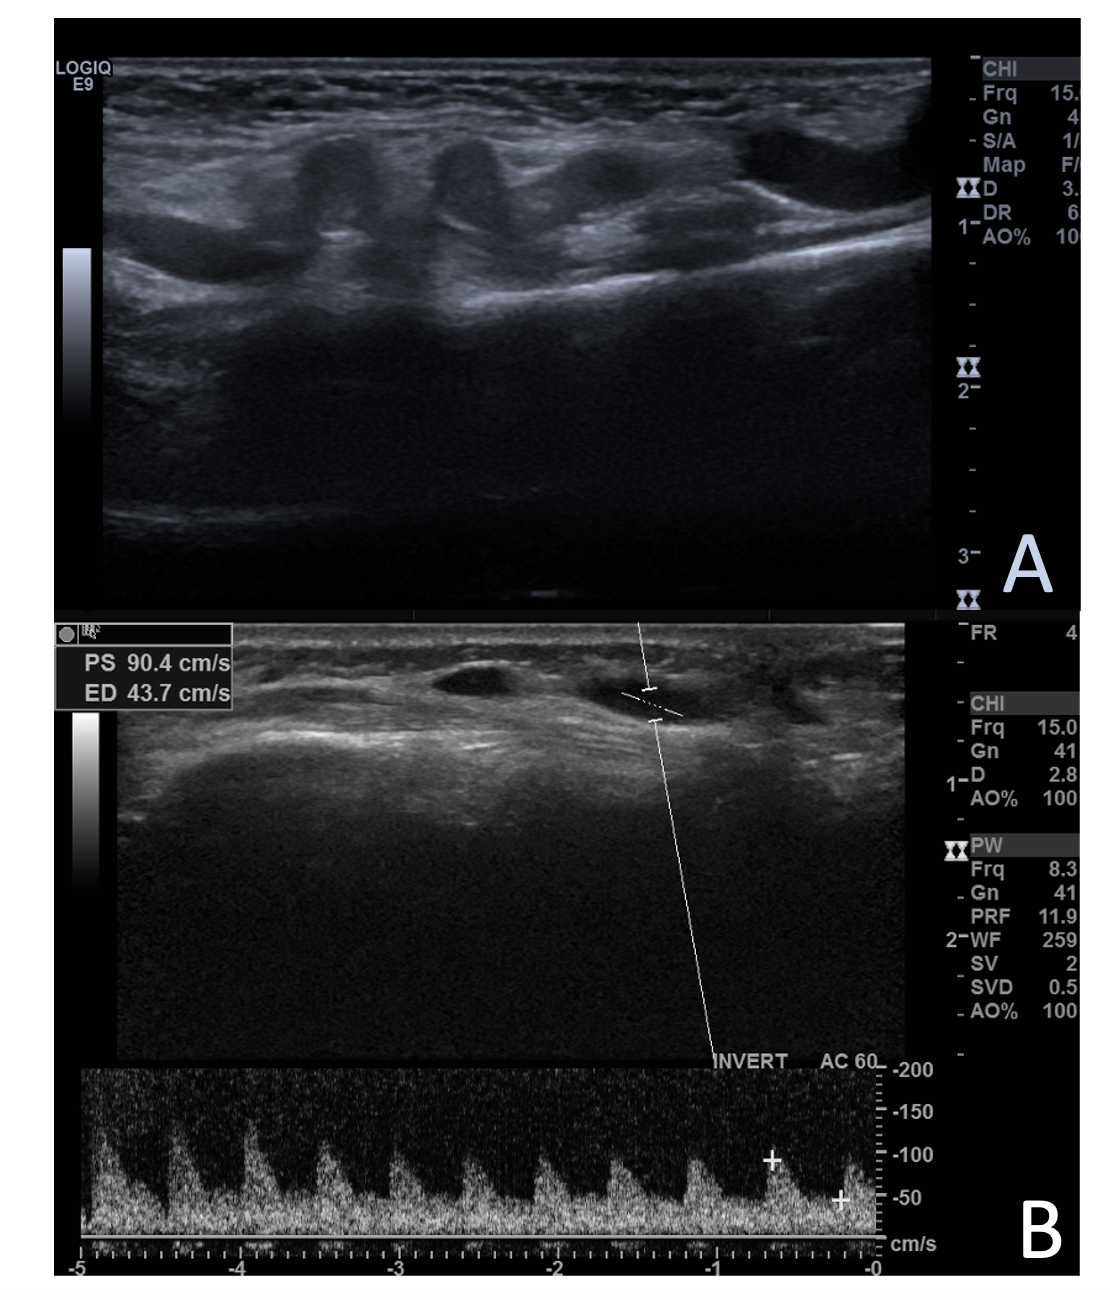

She was hospitalized for 23 days at her local hospital and 67 days at our hospital. Extensive liver investigations did not yield any significant cause, with spontaneous improvement of hepatic function. The karyotype, however, did show a mosaic of 45, XO, 46 XX. An ultrasound further elucidated the mass, which showed a communication between an artery and a vein (Figures 1 and 2).

The infant underwent an angiography. The ascending aorta was catheterized retrograde with the Seldinger technique. After preparation, the right femoral artery was accessed via a #4 sheath and a 4 x 1 Cobra catheter, a 4 x 2 pigtail, and a 0.035" guidewire (Video 1). The angiography showed an arteriovenous communication between the radial artery and cephalic vein over the right wrist. She was referred to surgery with a good operative result.

The main differential diagnosis is pseudoaneurysm formation.6 Arteriography in combination with ultrasound and Doppler studies can be utilized to delineate the anatomy and help guide optimal treatment.7-8 n